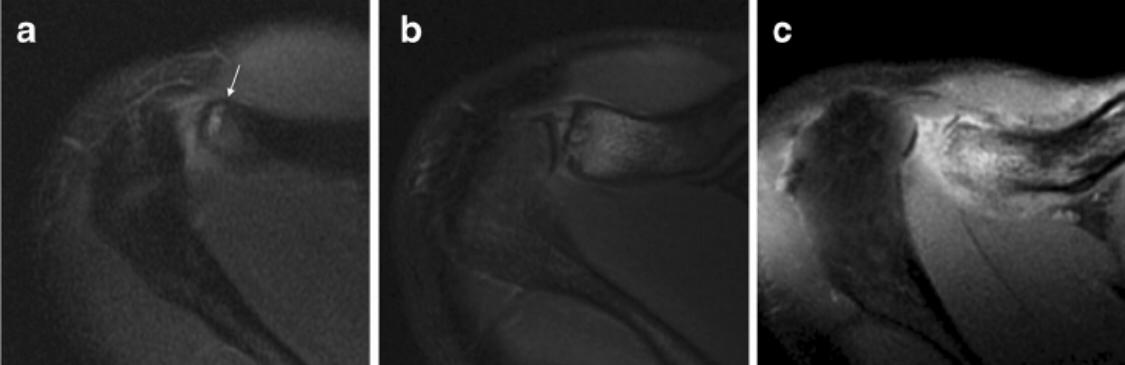

MRI is far more sensitive to detect DCO in an early stage. The most common MR-finding is bone marrow oedema in the distal clavicle, sometimes also in the articular part of the acromion, but less distinct.

Often, a hypointense line is seen in this area of clavicular bone marrow oedema, representing a subchondral fracture. AC-joint abnormalities are common, and include effusion, mild widening, intra-articular bone fragments and capsule hypertrophy. Other MR-findings are similar to those seen on radiographs, as described above.

DCO should be considered in the differential diagnosis of shoulder pain in the appropriate population. Therefore, analysis of MR arthrographic studies of the shoulder should not be restricted to evaluation of the rotator cuff and capsulolabral system, but the AC-joint should be scrutinised as well.